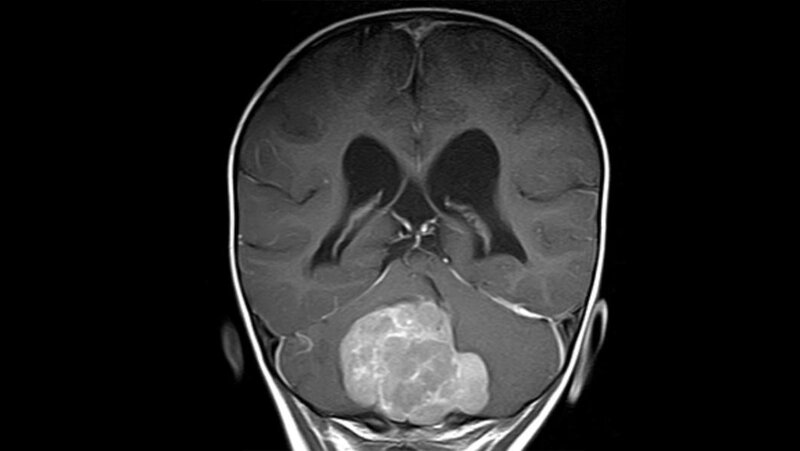

Das Medulloblastom ist einer der häufigsten soliden Tumoren im Kindesalter und der häufigste bösartige Hirntumor bei Kindern überhaupt. Laut Deutscher Hirntumorhilfe machen diese Tumoren bei Kindern und Jugendlichen etwa 20 Prozent, bei Erwachsenen nur 1 Prozent der Hirntumoren aus. Der Tumor wächst im Kleinhirn und kann lebenswichtige Hirnzentren durch sein Wachstum schädigen. Anhand von Gewebemerkmalen und genetischer Kriterien werden Medulloblastome heute in unterschiedliche Risikogruppen unterteilt, die einen völlig unterschiedlichen Verlauf nehmen können. Während bestimmte Subtypen aggressiv voranschreiten und Metastasen bilden, gibt es andere Formen, die durch eine intensive Kombinationstherapie aus Operation, Chemotherapie und Bestrahlung in der Regel geheilt werden können. Was bestimmte Tumoren auf zellulärer Ebene in die gutartigere oder bösartige Richtung lenkt, hat ein Forscherteam des Hopp-Kindertumorzentrums Heidelberg (KiTZ), des Deutschen Krebsforschungszentrums und des Universitätsklinikums Heidelberg (UKHD) jetzt mit einem neuartigen Verfahren untersucht.

Ein bestimmter Medulloblastomtyp, der sich einerseits durch seine guten Heilungschancen und gleichzeitig durch besondere strukturelle Eigenschaften seines Gewebes auszeichnet, diente ihnen dafür als Modell: Beim sogenannten Medulloblastom mit extensiver Nodularität (MBEN) grenzen sich innerhalb des Tumors kleine Gewebekammern ab, die weintraubenartig zusammenhängen. Tumorzellen, die sich in diesen Knoten befanden, so zeigte die Studie, waren nicht mehr teilungsaktiv und ihr genetisches Programm ähnelte denen ausgereifter Hirnzellen. In den Zwischenbereichen identifizierten die Wissenschaftlerinnen und Wissenschaftler dagegen unterschiedliche Zelltypen: Neben Immun- und Bindegewebszellen befanden sich dort auch deutlich aggressivere Tumorzellen, die sich weiterhin unkontrolliert teilten und deren genetisches Programm eher denen schnell wachsender Medulloblastome und unreifer Nervenzellen ähnelte. Im Laufe ihrer Wanderung in die Knoten reiften die Krebszellen jedoch wieder zu nervenähnlichen Zellen aus und teilten sich nicht mehr.